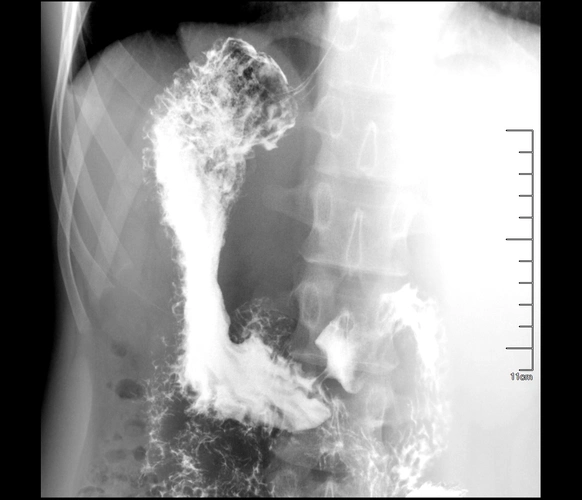

外压性改变;充盈缺损;憩室;腔内龛影?

直接征象:龛影;急性期:粘膜水肿带(粘膜线,项圈征,狭颈征);慢性期

可发现十二指肠憩室表现为突出于肠壁的袋状龛影,轮廓整齐清晰,边缘

十二指肠溃疡:多见于球部;影像表现:龛影,钡点,变形溃疡周围杵状粘膜